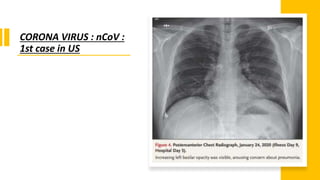

Change in respiratory status was noticed starting on the evening of

hospital day 5, when the patient’s oxygen saturation values as

measured by pulse oximetry dropped to as low as 90% while he

was breathing ambient air

Given the changing clinical presentation and concern about

hospital-acquired pneumonia, treatment with vancomycin (a 1750-

mg loading dose followed by 1 g administered intravenously every

8 hours) and cefepime (administered intravenously every 8 hours)

was initiated.

Given the radiographic findings, the decision to

administer oxygen supplementation, the patient’s

ongoing fevers, the persistent positive 2019-nCoV RNA at

multiple sites, and published reports of the development

of severe pneumonia at a period consistent with the

development of radiographic pneumonia in this patient,

clinicians pursued compassionate use of an

investigational antiviral therapy